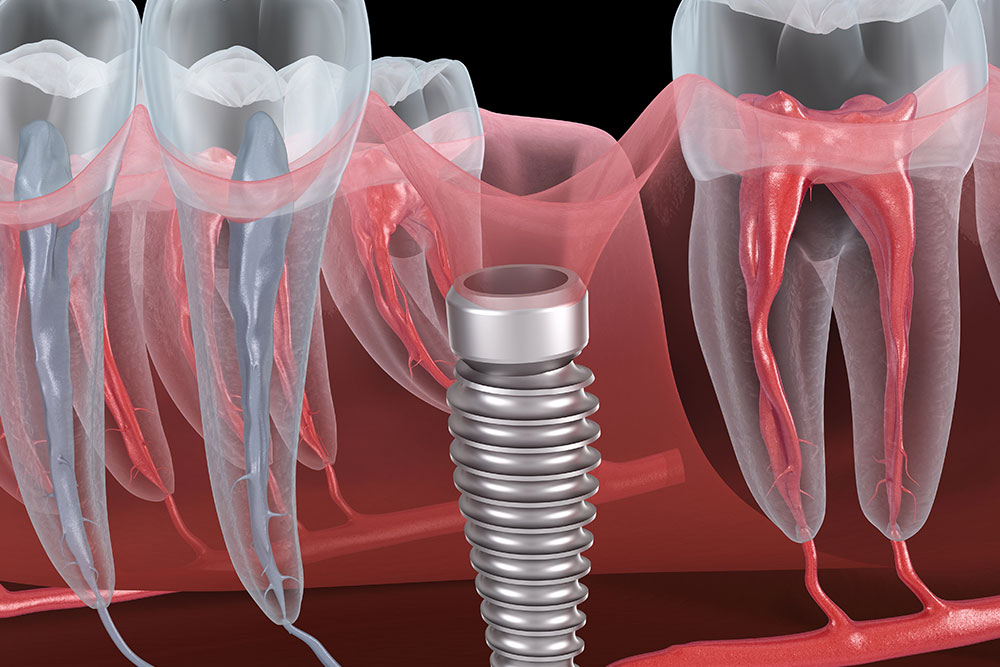

5 Common Mistakes To Avoid When Placing Dental Implants

Dental implants offer patients permanent solutions for missing teeth, but correctly placing them takes skill, …

Dental implant procedures require precision, expertise, and the right set of tools. Using high-quality dental …